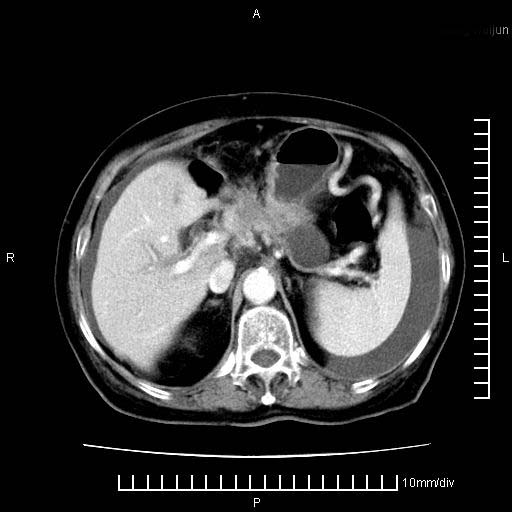

标题: CT28280:腹部增强:女性,80岁

上腹疼痛月余,外院核磁诊断胰腺癌。现临床示右下腹可明显触及包块,可片子上怎么没有看到?

1.胰腺颈体部癌。

胰腺体部癌累及周围器官,腹膜、粘连

胰腺体部癌累及周围器官,腹膜、粘连,临床摸到的可能是粘的组织

胰腺结构模糊,胰尾部见囊性包块,周围脂肪密度增高,左肾前筋膜增厚,胸水、腹水。不符合胰腺ca伴腹膜腔转移。考虑胰腺炎伴假性囊肿形成、胸腹腔积液。

1)考虑胰腺癌并胰腺假性囊肿形成。2)肝内低密度灶,不排除转移。3)右肾盂积水。4)腹水。5)右侧胸腔积液并右肺下叶部分膨胀不全。